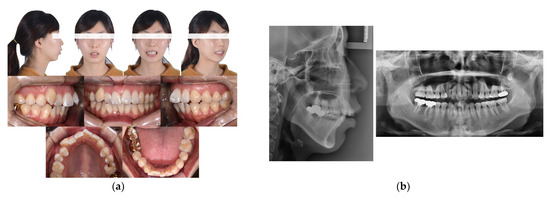

Case Report